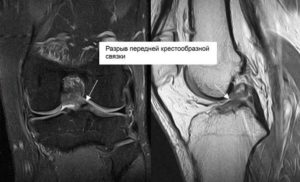

- МРТ. Также весьма эффективным методом является магнитно-резонансная томография. При её проведении используются электромагнитные волны, которые позволяют визуализировать не только плотные, но и мягкие материи. Благодаря этому можно отследить разновидность травмы.

Магнитно-резонансная томография позволяет увидеть все повреждения сустава, в том числе крестообразных связок, в 3d проекции.

- МРТ. Магнитно-резонансная томография является наиболее точной методикой подтверждения диагноза в отношении дегенерации связок колена с вероятностью до 95%;